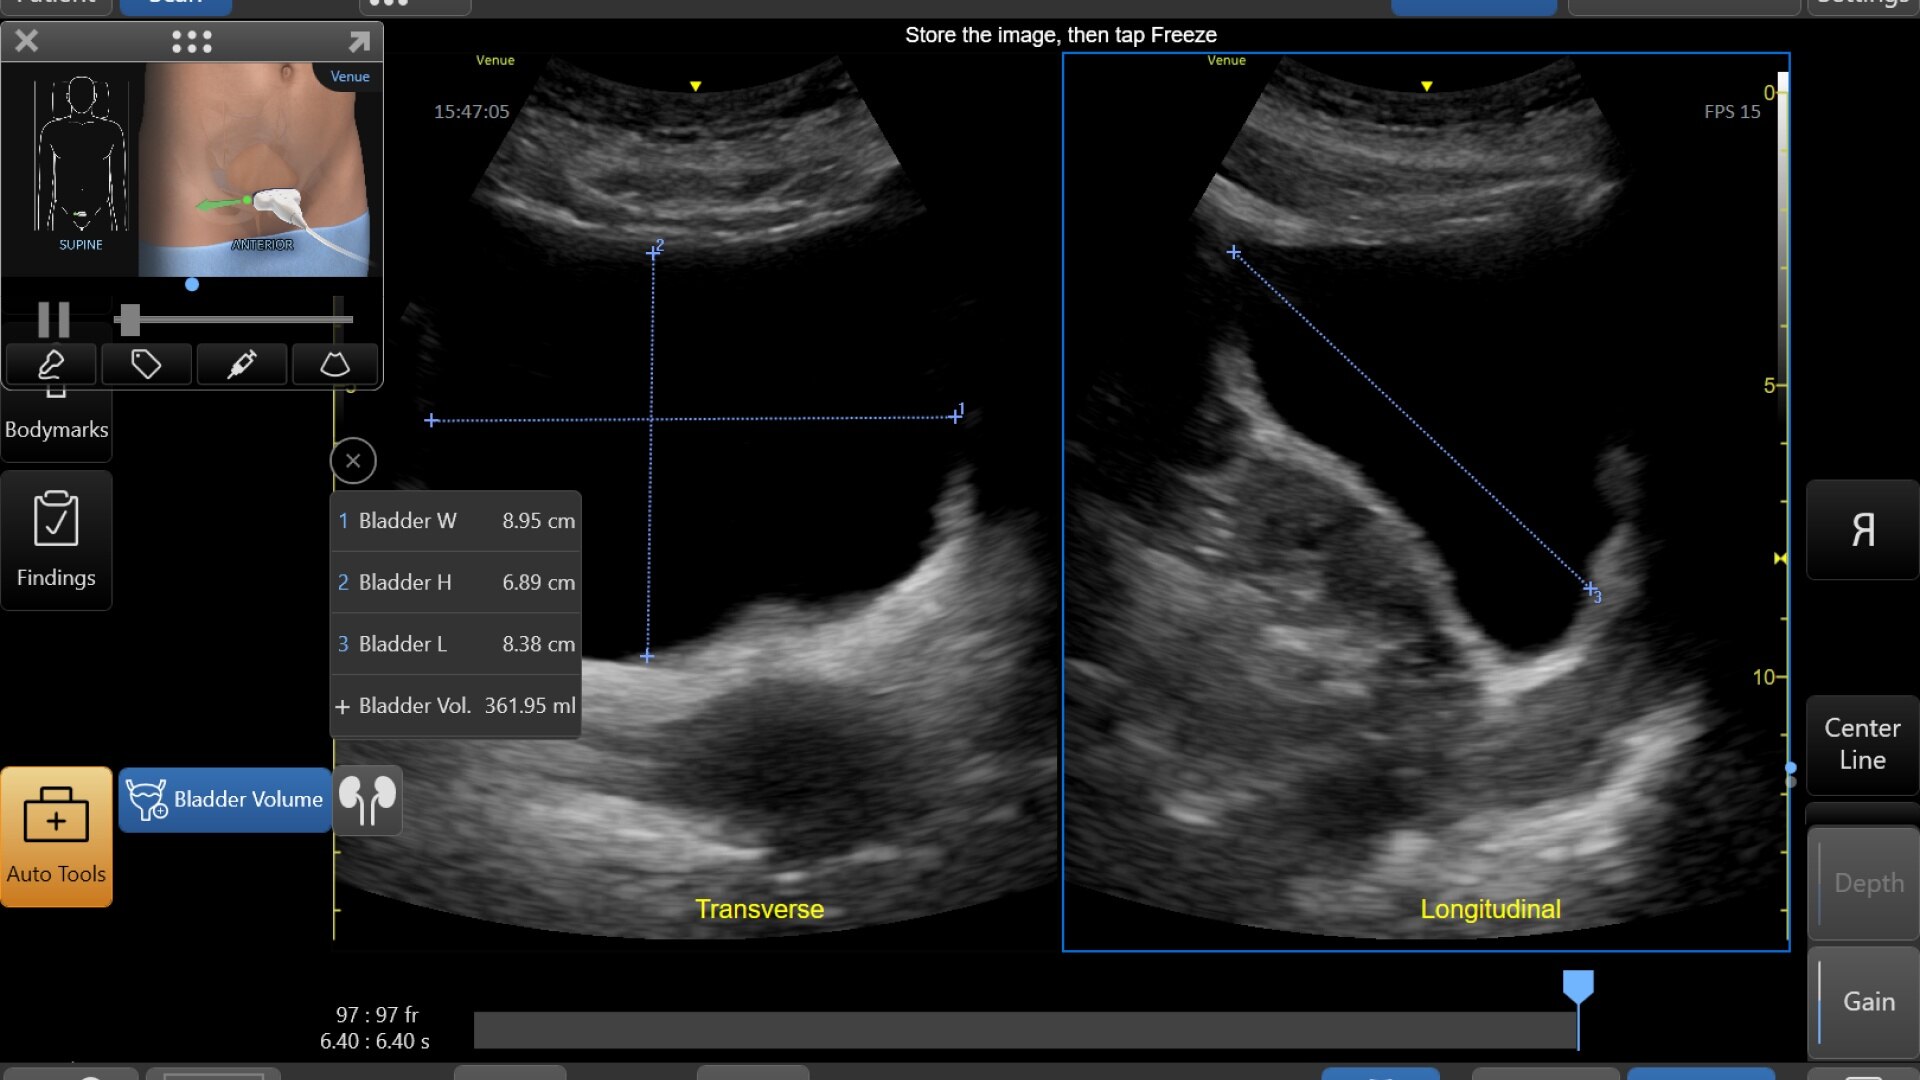

BLADDER VOLUME TOOL

Quick and easy exam documentation

This simplified workflow tool features reference images as guidance and supports clinicians in calculation of the bladder volume. The tool is designed to guide bladder volume measurements to make it simple and fast.